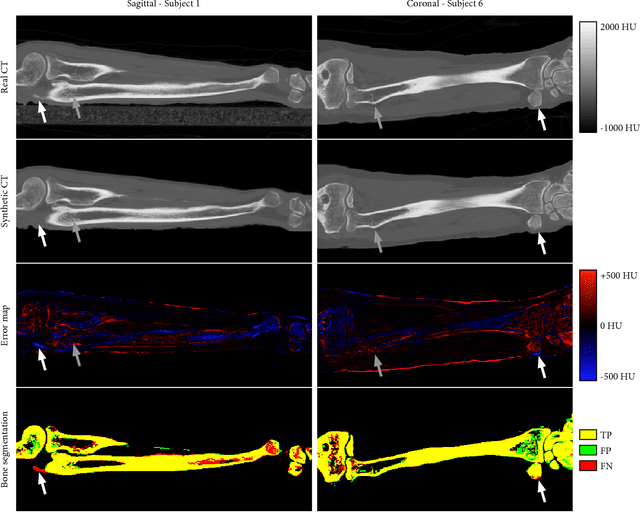

Abstract:Purpose: To assess the feasibility of deep learning-based high resolution synthetic CT generation from MRI scans of the lower arm for orthopedic applications. Methods: A conditional Generative Adversarial Network was trained to synthesize CT images from multi-echo MR images. A training set of MRI and CT scans of 9 ex vivo lower arms was acquired and the CT images were registered to the MRI images. Three-fold cross-validation was applied to generate independent results for the entire dataset. The synthetic CT images were quantitatively evaluated with the mean absolute error metric, and Dice similarity and surface to surface distance on cortical bone segmentations. Results: The mean absolute error was 63.5 HU on the overall tissue volume and 144.2 HU on the cortical bone. The mean Dice similarity of the cortical bone segmentations was 0.86. The average surface to surface distance between bone on real and synthetic CT was 0.48 mm. Qualitatively, the synthetic CT images corresponded well with the real CT scans and partially maintained high resolution structures in the trabecular bone. The bone segmentations on synthetic CT images showed some false positives on tendons, but the general shape of the bone was accurately reconstructed. Conclusions: This study demonstrates that high quality synthetic CT can be generated from MRI scans of the lower arm. The good correspondence of the bone segmentations demonstrates that synthetic CT could be competitive with real CT in applications that depend on such segmentations, such as planning of orthopedic surgery and 3D printing.